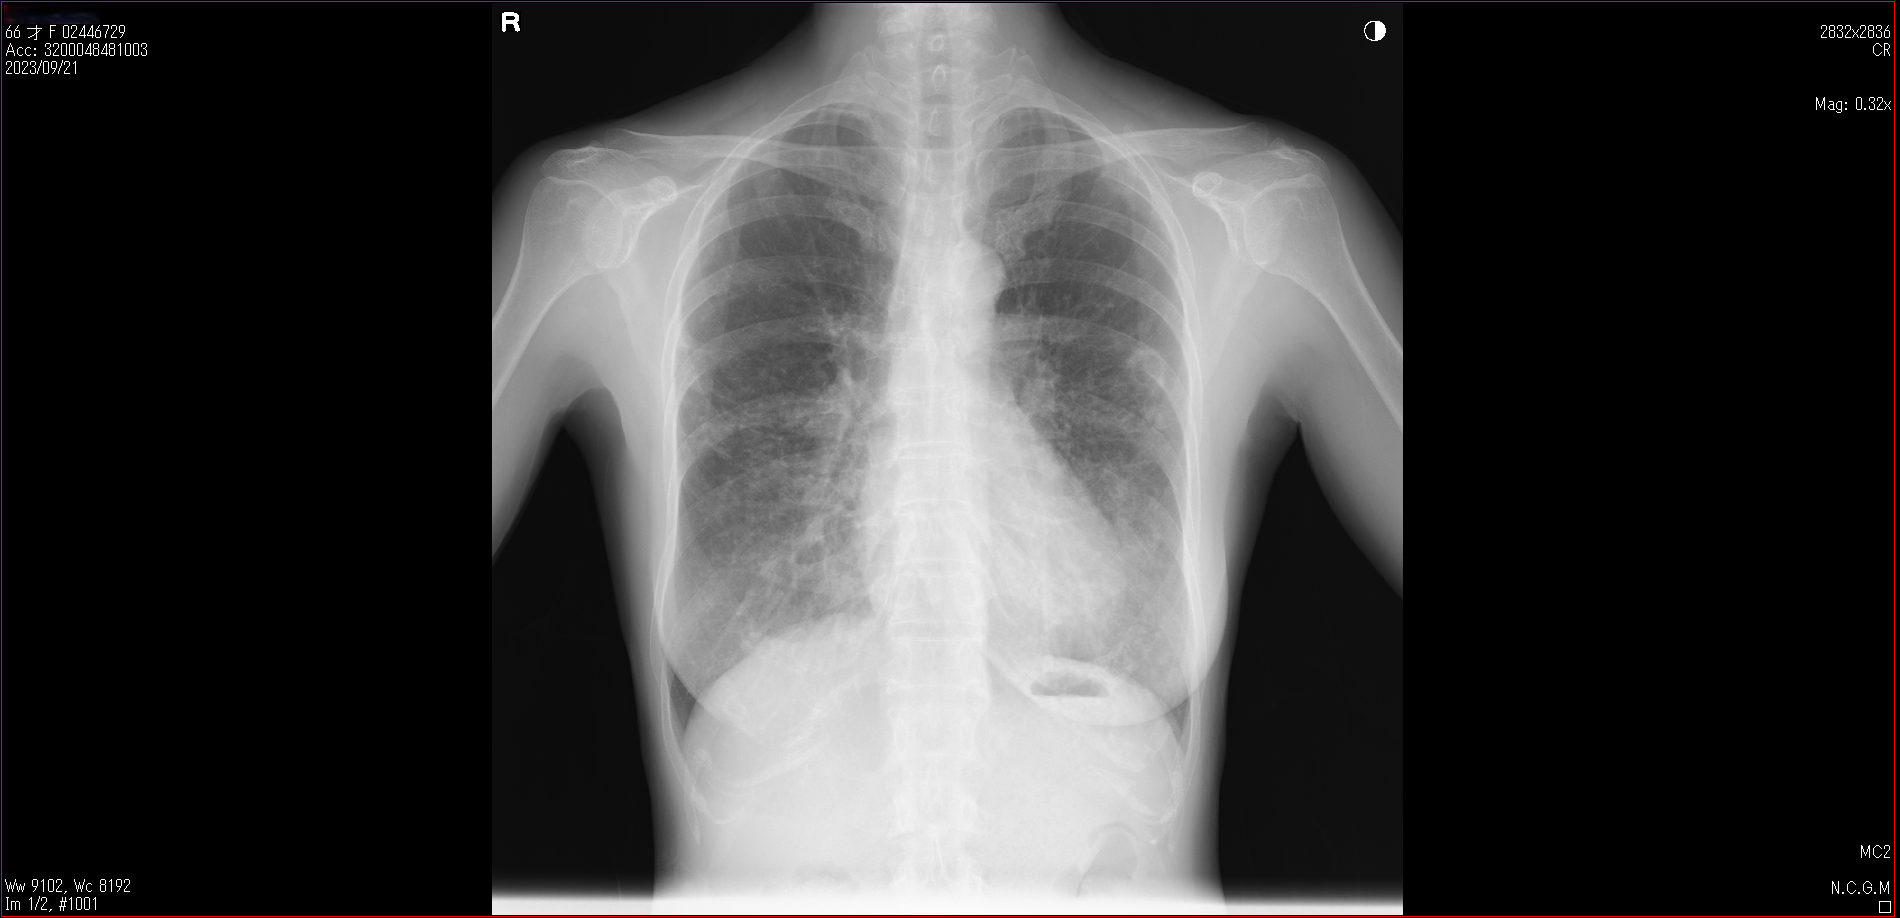

肺X線画像

2023

- 2023.09.21 入院加療の必要ありと診断された画像(国立系病院)